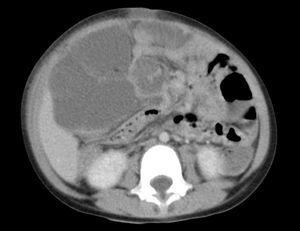

Al persistir la fiebre alta y la afectación del estado general se inicia tratamiento empírico con ceftriaxona intravenosa a las 48 h del ingreso. Al quinto día de ingreso, ante el empeoramiento del estado general junto con aumento de la distensión abdominal, se realiza ecografía abdominal urgente que muestra estructura quística septada de gran tamaño en hemiabdomen derecho (fig. 1) y tomografía computarizada (TC) abdominal donde se observa una gran masa abdominal de densidad líquido que desplaza el resto de estructuras abdominales (fig. 2). La analítica en este momento muestra una proteína C reactiva de 32,5 mg/dl con un hemograma y fórmula similar a la analítica del ingreso.

Figura 2.TC abdominal que muestra estructura de contenido líquido con septos que desplaza estructuras vecinas y provoca distensión abdominal.